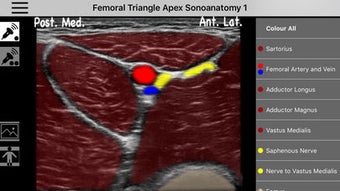

AnSo Anestesia Sonoanatomía es una aplicación para iPhone que proporciona una comprensión integral de la sonoanatomía relevante para el anestesista. Con más de 250 imágenes de ultrasonido y 1500 superposiciones de color de sonoanatomía, esta aplicación es un recurso conveniente diseñado para ayudar a los anestesistas a identificar la sonoanatomía común de manera eficiente en el tiempo dentro del ajetreado quirófano. Creado por anestesistas en ejercicio con interés en la enseñanza de la ecografía y la anestesia regional, AnSo proporciona múltiples ejemplos de la sonoanatomía ya que cada individuo es diferente.